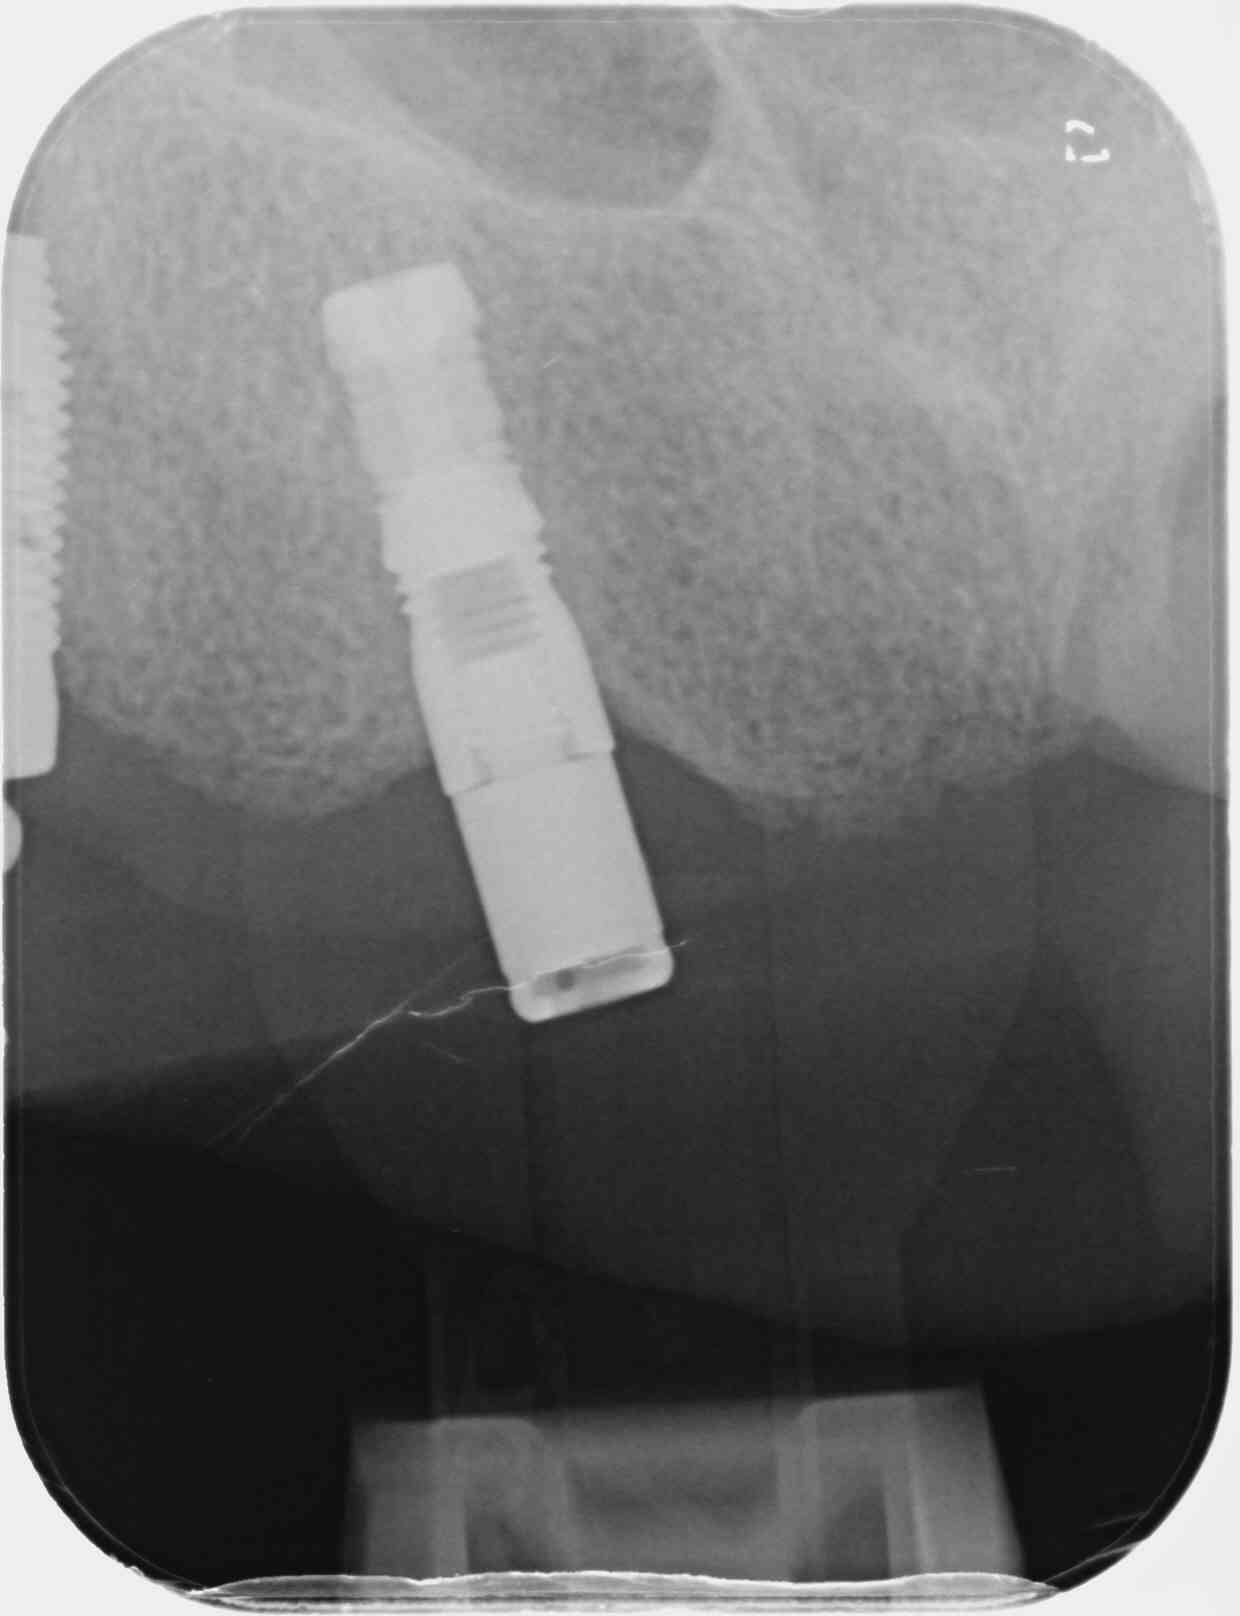

Je suis aussi bloqué sur l'identification d'un implant. J'ai cherché un peu sur le net sans résultat. Implant posé vers 1995, avec un pilier Locator qui est en place depuis 10 ans.

Un grand merci d'avance à celle ou celui qui pourrai m'aider.

bon et bien je viens de tout passer en revue....et nada....

bizarre comme implant...un corps qui fait penser à un Frialit...mais une connexion qui ressemble à celle d'un steri-oss...

donc à moins qu'un nonolien ait déjà utilisé cet implant et le reconnaisse...

Pour les curieux, on a réussi à identifier l'implant : SOREM Ortho, non indexé, connectique de type Denar. Implant fabriqué à quelques centaines d'exemplaires seulement et bien sur aucune possibilité de le réutiliser pour une future prothèse car la boîte a fermé. Je vais devoir le déposer ainsi que son frère jumeau secteur 20 dont l'apex est dans les fosses nasales.